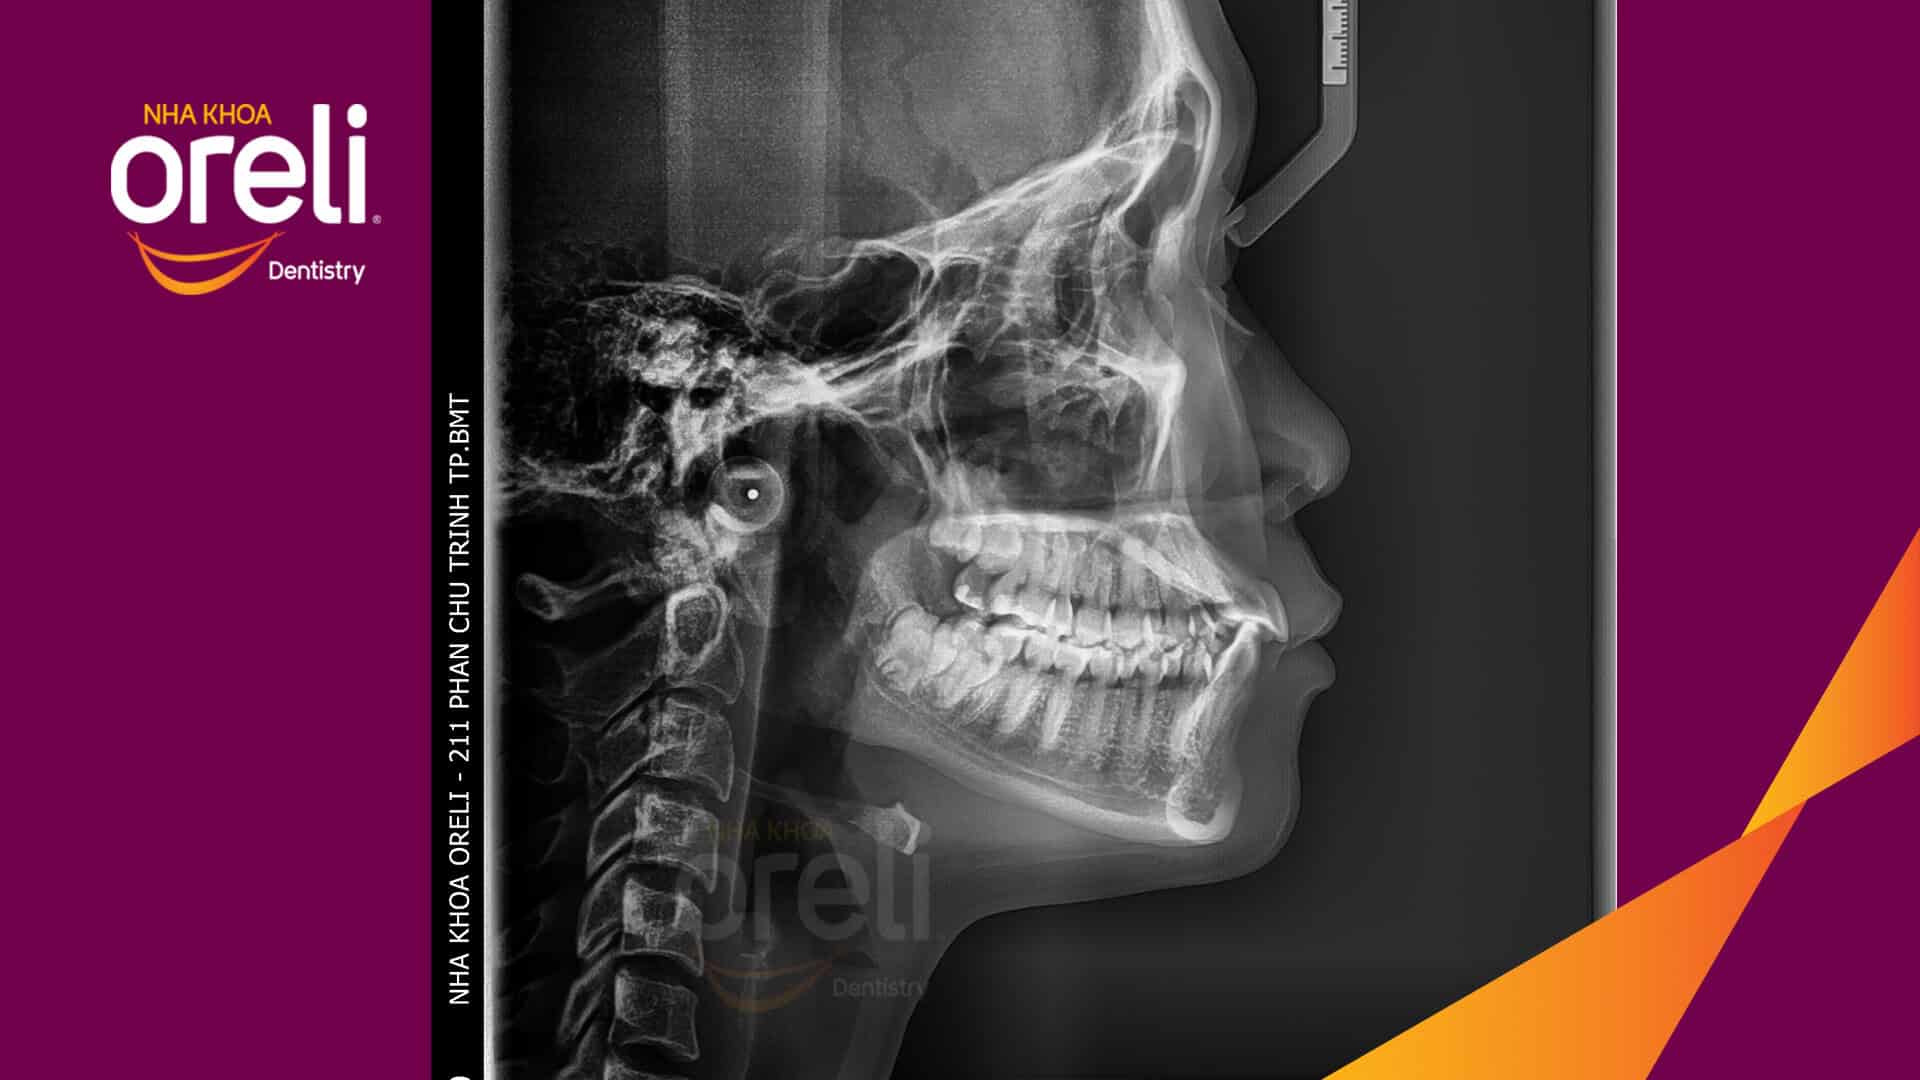

Kết quả: Khớp cắn đúng nụ cười tự nhiên, góc mặt nghiêng đẹp

Trong trường hợp này độ nhô môi lớn, góc mũi môi nhọn, môi trên và dưới trượt ra trước so với đường thẩm mỹ E của Rickket, trục răng cửa hàm trên ngả trước nhiều. Việc nhổ răng 4 để giảm hô được thực hiện.